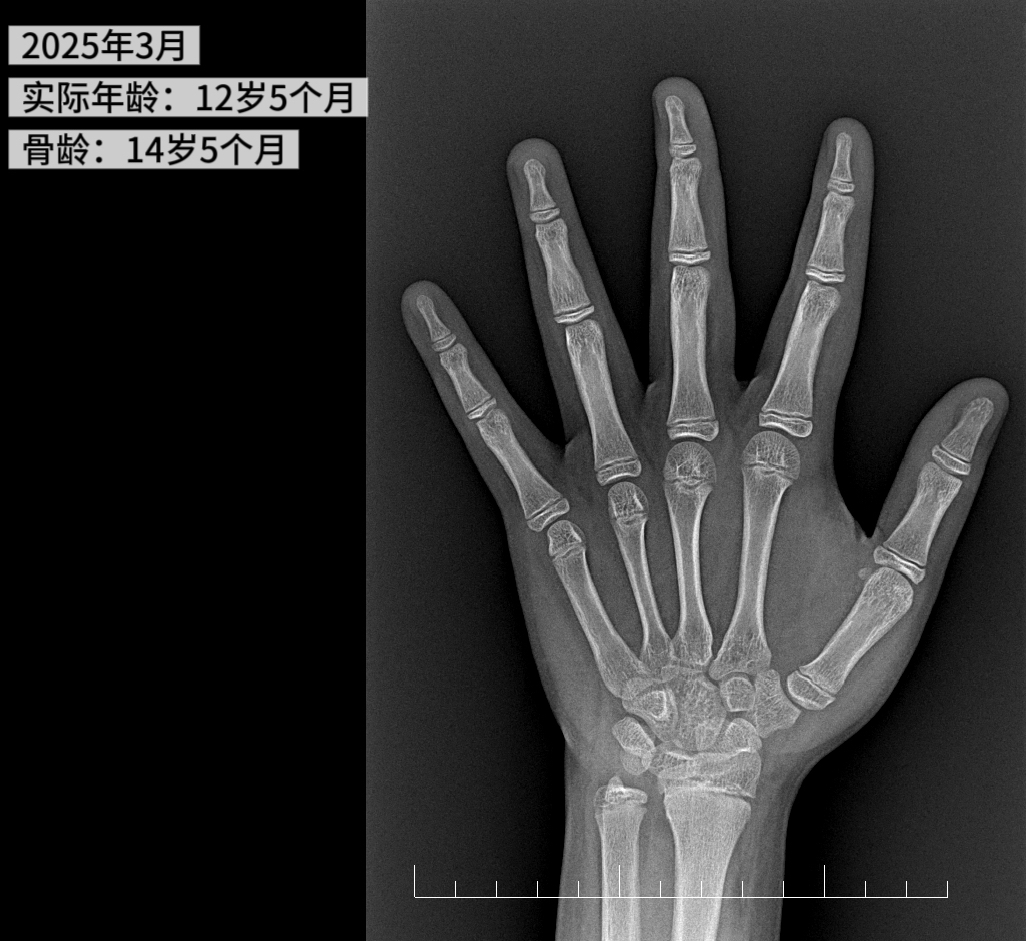

今年 3 月,草莓医院儿保科周丹丹医生诊室来了一个大胖小子,孩子父母告诉医生,儿子小铭(化名)今年 12 岁零 5 个月,从 2019 年起,因为宅在家里不出门,狂吃各种美食,特别是高糖、高碳水的食物,比如炸鸡、薯条、可乐、奶茶,糕点这些,晚上还经常加餐,导致体重飙升了 20 斤,达到了快 180 斤!家里人也督促了减肥,但是一直卡在 175 斤就没动弹过,后来想着小孩子嘛正是长身体的时候,等到了青春期自然就会瘦下来的,所以从来没有带孩子来医院做过任何检查。可没曾想,眼看着儿子的体重日渐增长,但是身高却始终在原地踏步,比班上的同龄人矮了大半个头,孩子也因为体重和身高问题在学校频频受到排挤。这时才想着是不是应该带孩子接受一次正规且系统的儿童体检,排查一下健康问题!

在完善肥胖相关检查后,发现小铭目前有明显的「脂肪肝」,骨龄超前了 2 岁,空腹胰岛素水平偏高,提示「高胰岛素血症」!拿到这一结果,小铭和爸爸妈妈都傻了眼,没想到体重这个事对健康的影响这么大,还好带孩子来做体检了,不然继续耽搁下去不知道会出现多严重的后果!